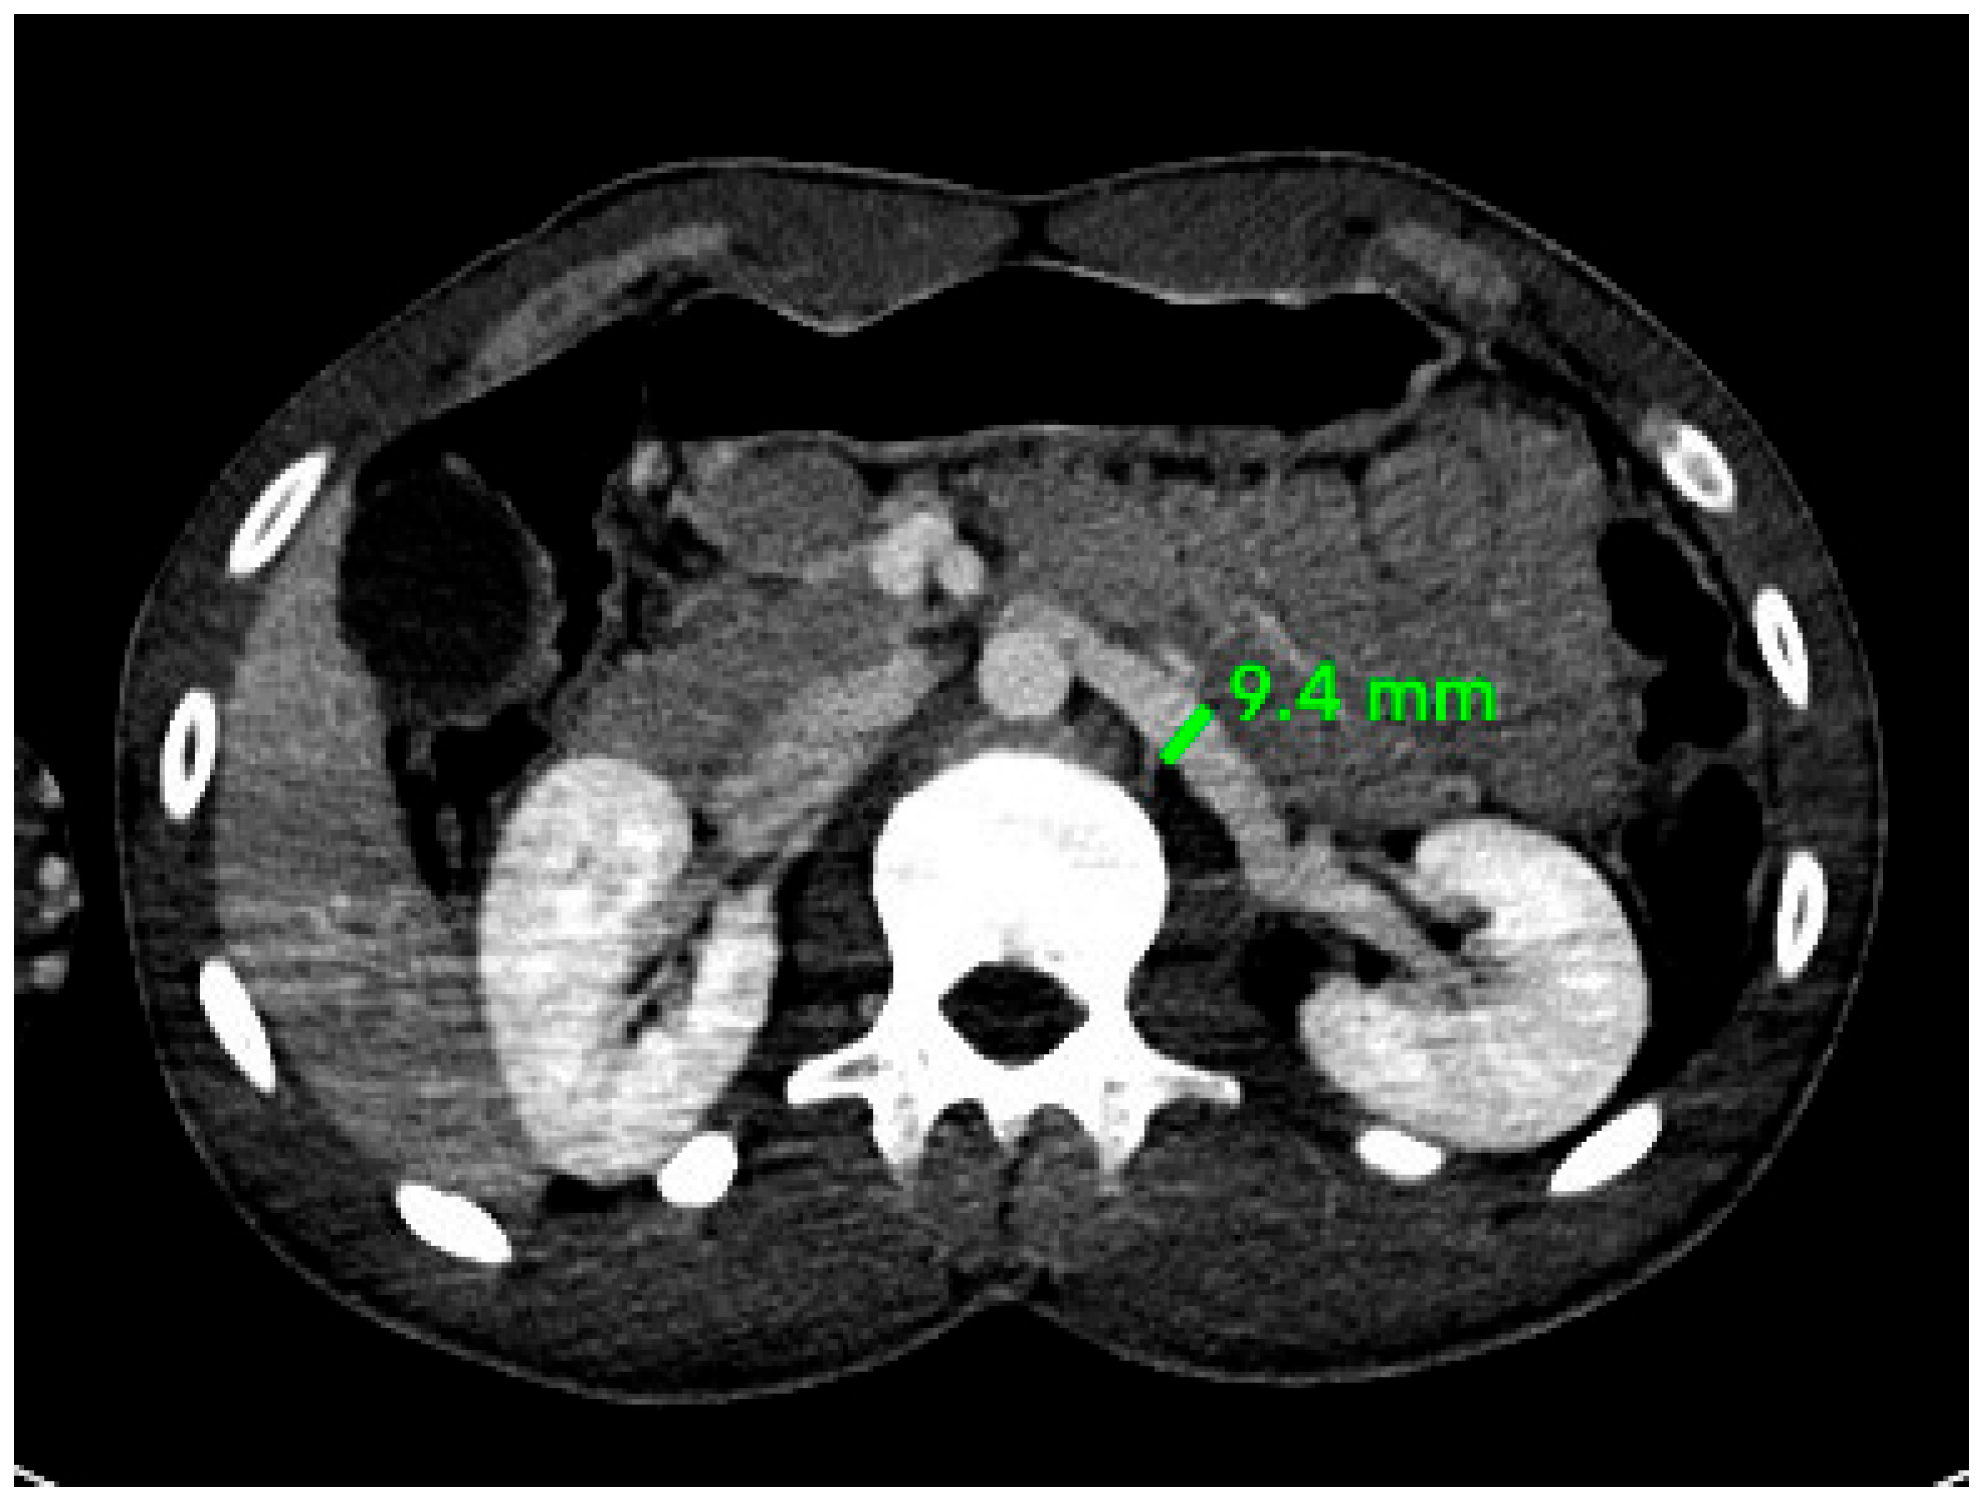

| Right RA | 4.62 ± 0.93 mm | 4.22 ± 0.79 mm | 0.020 |

| Muscat, Oman (our study) | 2025 | 128 (92M, 36F) | 4.62 mm (M), 4.22 mm (F) | 5.07 mm (M), 4.64 mm (F) | This study |